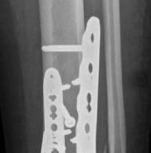

Fig 2.2-6a–b Immediate postoperative x-rays showing restoration of the ankle mortise and distal tibia alignment through anatomical and stable fracture fixation.

1. AP view.

2. Lateral view.